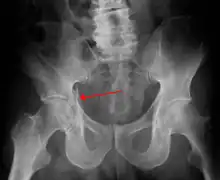

Posterior wallThis is the most common variety of acetabular fracture. It typically occurs due to dashboard injury; when a person travelling in a vehicle involved in a head-on collision, the force applied over the flexed knee travels along the femur bone to the head of the femur, breaking the posterior wall of the acetabulum. The head of the femur is dislocated outside the joint. T shapeWhen a transverse fracture also had a vertical fracture line, it is called a T shape fracture. Here the innominate bone is broken in such a way that all three parts of it, the ilium, the ischium and the pubis are separated from one another. This is a three part fracture. Though both columns are broken, the weight bearing dome is still attached to the main part of the ilium and hence it is not a true fracture of both columns.

• Posterior wall fracture: Iliac oblique and obturator oblique views